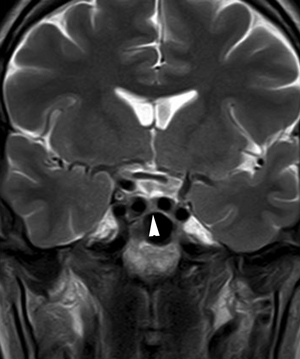

Figura 7. Corte coronal, secuencia T2w, muestra que la hipófisis ocupa la porción central de la fosa pituitaria (punta de flecha), con ambas arterias carótidas internas aproximándose a la línea media, lo que corresponde a una variante anatómica, que debe identificarse antes de realizar una cirugía por vía transesfenoidal.